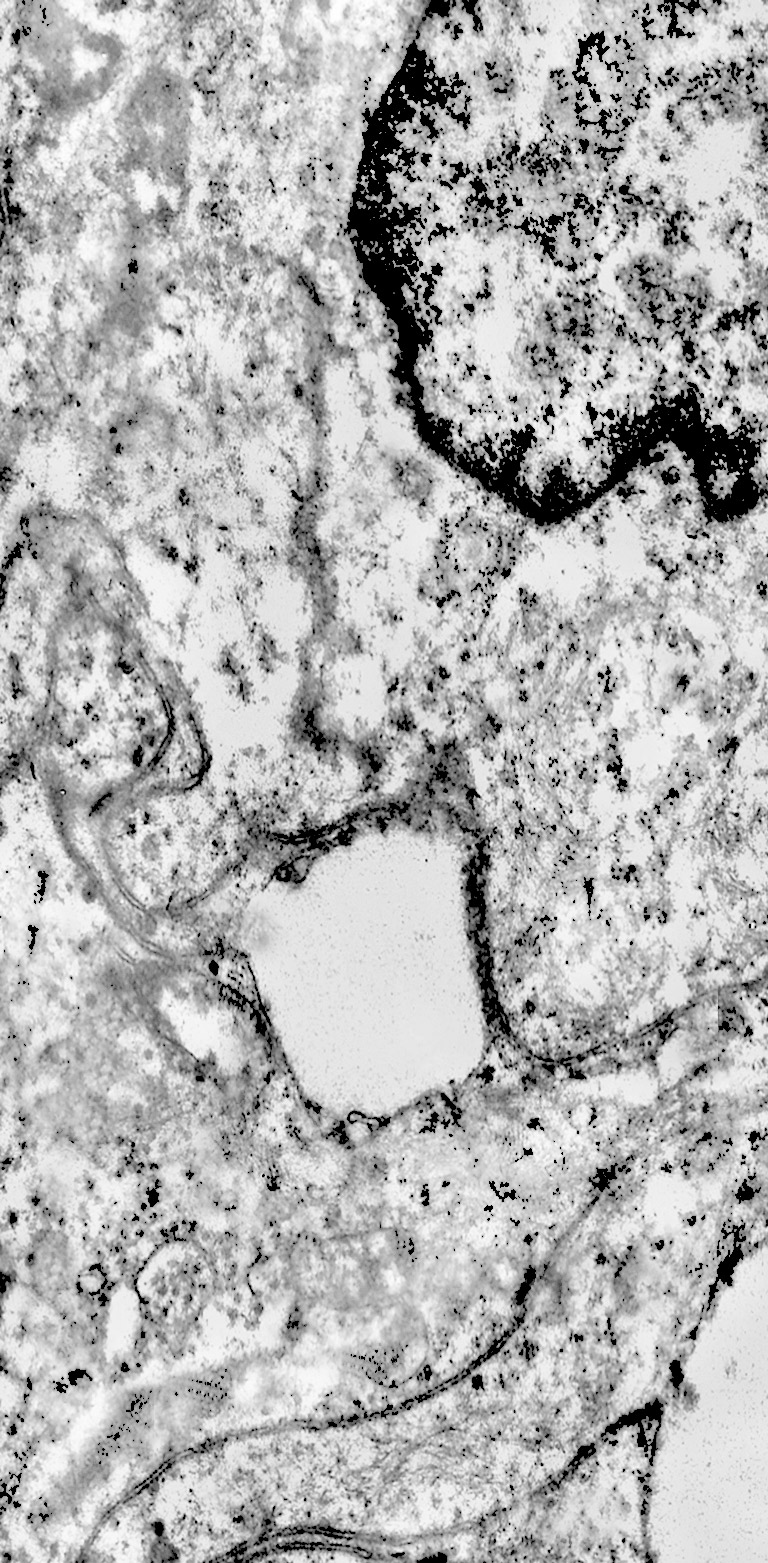

Alcune cellule meningoteliali sono sedi, sopratutto a livello delle fasce periferiche, di ampie vescicole, di forma irregolare le quali sono demarcate da una membrana a mono-strato; gli spazi di queste vescicole sono in buona parte occupati da materiale amorfo, da frammenti filamentosi e da organuli intracitoplasmatici,tutto sottoposto a degradazione.

E’ possibile anche il reperto di elementi cellulari aventi il citoplasma occupato da ampie vescicole,delimitate da una membrana a monostrato, le quali sono ricolme di materiale amorfo,da strutture granulo-filamentose o da frammenti di organuli.

Non è raro il riscontro di cellule meningoteliali le quali hanno il citoplasma in buona parte occupato da una formazione cava,irregolarmente rotondeggiante; questa è delimitata da una spessa membrana ed è occupata da frammenti di citoplasma e da singoli organuli,tutto in corso di degradazione.